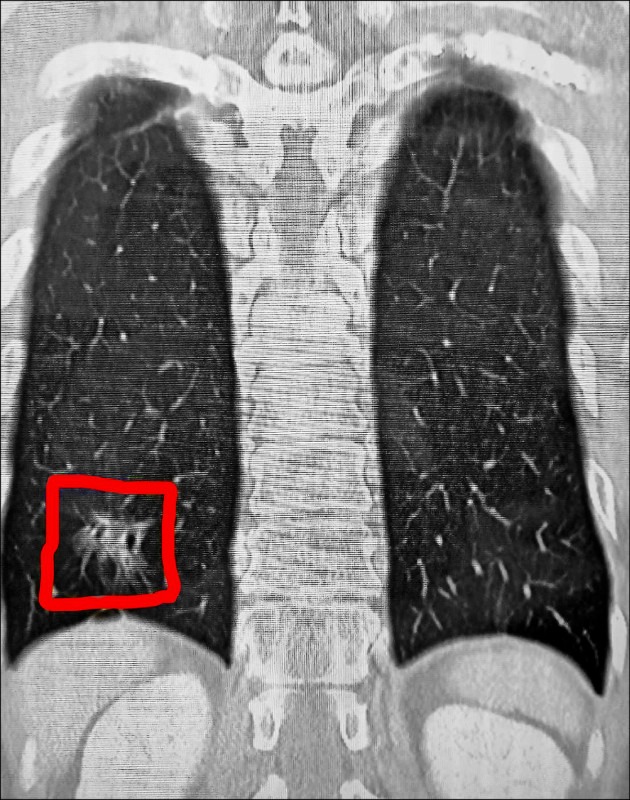

台中70歲老翁「撞斷肋骨」!醫見X光「見更可怕殺手」意外救了一命

台中一名70歲陳姓老翁日前遭遇嚴重車禍,左側第3到第7根肋骨全數斷裂,還出現胸壁挫傷跟血胸狀況,幾乎無法正常呼吸。他被緊急送往國軍台中總醫院急救,醫療團隊準備為他進行「胸腔鏡輔助肋骨骨折復位矯正鋼板內固定手術」,沒想到術前檢查電腦斷層時,胸腔外科主任謝志明竟在影像中發現更可怕的東西。

根據《TVBS新聞網》、《自由時報》報導,謝志明主任仔細分析陳先生的斷層掃描影像,赫然發現他的右下肺葉出現疑似癌症的病灶。當時陳先生的車禍傷勢在住院治療2週後就順利出院,但那塊毛玻璃樣的肺部陰影卻讓醫師相當擔憂。由於肺腺癌被稱作「隱形殺手」,早期幾乎沒有任何症狀,許多患者發現時往往已經來不及了。

圖片來源:國軍台中總醫院

3個月後陳先生回診追蹤肋骨復原狀況,謝醫師發現那處病灶依舊存在,立刻安排他接受第2次「胸腔鏡微創手術」將病灶切除。病理化驗結果證實醫師的判斷沒錯,陳先生確實罹患肺腺癌第1期。謝醫師解釋,一般胸部X光很難偵測到1公分以下的微小病變,許多肺癌病患確診時病情已經相當嚴重。